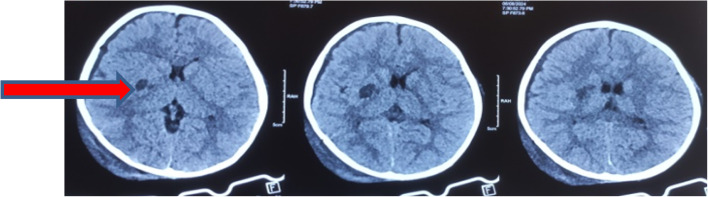

Case presentation: A 3 years old male with recent history of traumatic head injury following road traffic accident presented with weakness of left upper and lower limbs. On diagnostic evaluation there was right sided basal ganglia acute infarct. On further investigations basal ganglia infarct was secondary to moya moya disease. Patient was managed conservatively with single low dose anti platelets therapy, anti epileptic and was discharged with good functional outcome.